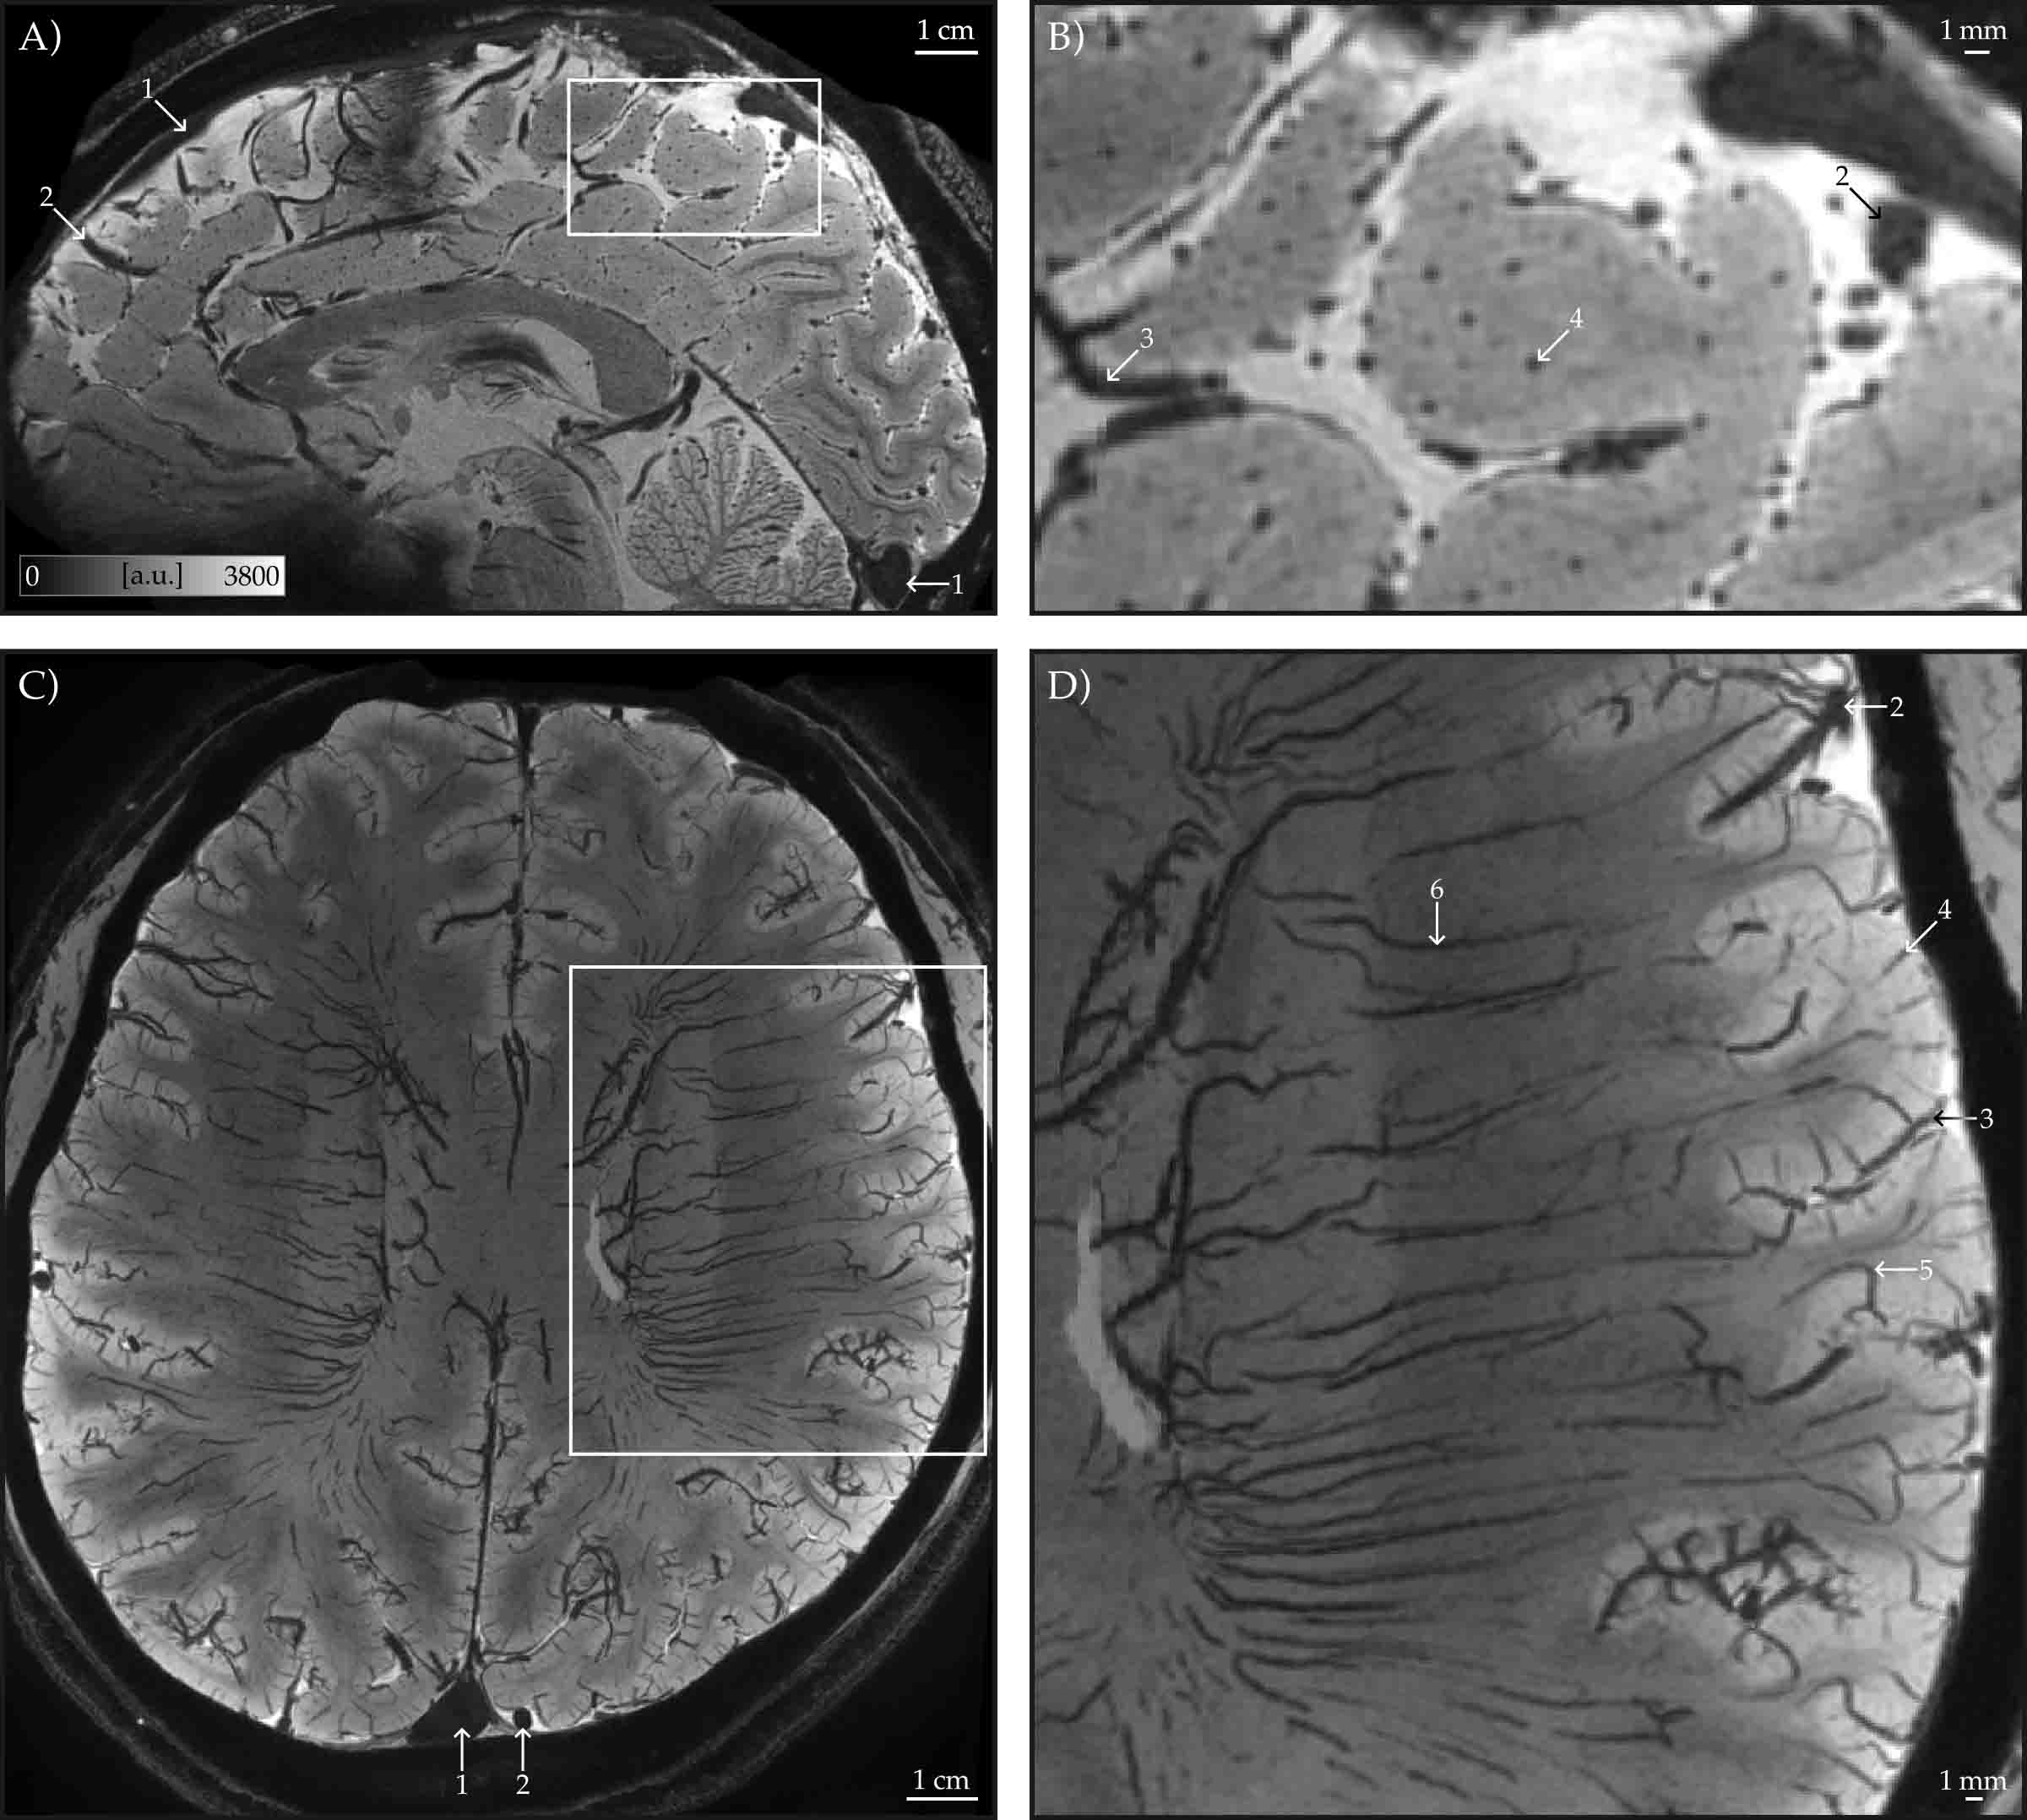

The team used ultra-high-field 7 Tesla MRI to capture whole-brain images at a resolution of 0.35 millimetres in just seven minutes, allowing tiny veins within the cerebral cortex to be visualised across the entire living brain. Blood vessels, particularly veins, strongly influence functional MRI (fMRI) signals, which are widely used to study brain activity and disease. Until now, limited visibility of the brain’s venous structure made it difficult to interpret scans accurately or detect subtle vascular changes linked to stroke, dementia, and neurodegeneration.

To overcome these challenges, the researchers developed both a rapid imaging protocol and advanced processing techniques. These methods distinguish between large surface veins, smaller pial veins, and veins embedded within the brain’s grey matter, helping clinicians separate vascular effects from true neural signals.

The research also recreated classic vascular maps first produced by anatomist Henri Duvernoy and produced the first whole-brain maps of intracortical veins at this level of detail, marking a significant advance in brain imaging.